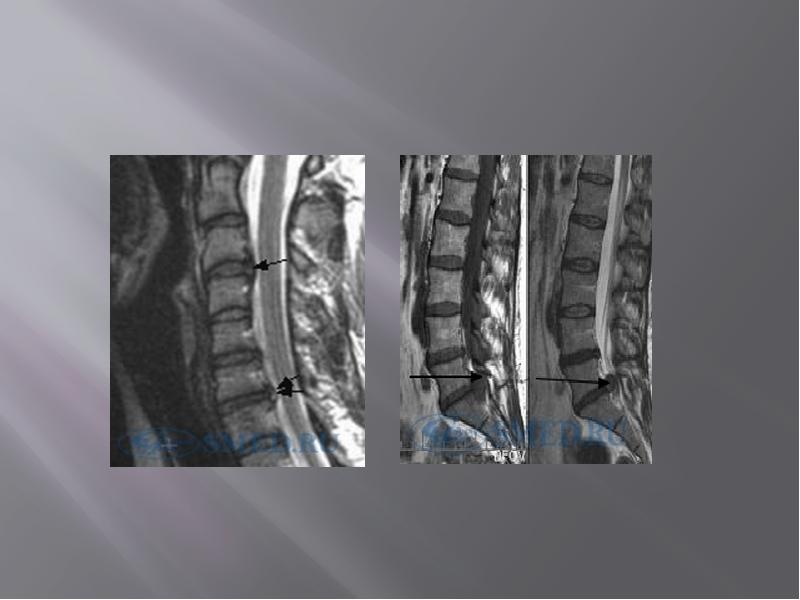

- 48. МРТ – исследование в большинстве случаев позволяет выявить: МРТ – исследование